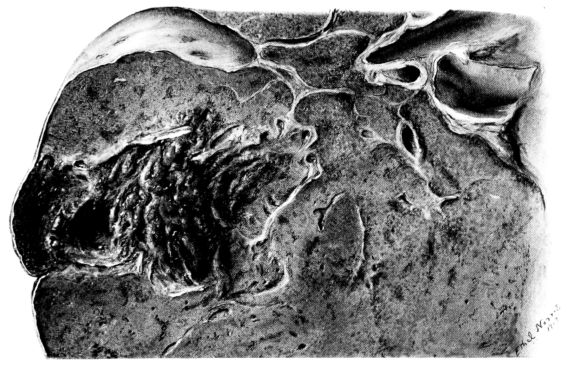

Early in the disease the congestion and the hemorrhages that have been described in the mucous membrane of the nasopharynx (14 and 94) are also conspicuous features in the lining of the trachea and bronchi (Fig. I). This membrane is swollen, turgid, red, and covered by a copious, mucous exudate which may be clear, but much more frequently is blood-stained or opaque and yellowish in color. The blood, variable in amount, may be fresh and red; and after the mucous exudate on the surface is removed, more intense red foci stand out on the congested base (47, 90, 157). Frequently, as the bronchi are approached, the red color of the mucosa becomes more intense and may have a garnet tinge. Membranes such as are encountered in the more usual necrotizing inflammatory processes, like diphtheria, have not occurred in the trachea and larger bronchi in this series (108, 128, 157).[3] The exudate peels off readily, and as indicated above, leaves a velvety red surface, 14dotted here and there with darker or more intensely red foci. Small ulcerations of the mucosa occur, but are inconspicuous (82, 156). As the finer ramifications of the bronchi are approached, the accumulation of the exudate in their lumina becomes more and more marked, and on cross section of the lung, they often stand out conspicuously on account of their increased size and projecting, seromucous, blood-stained content (101, 149, 162).

It is remarkable how long this picture in the trachea and bronchi may persist without showing any marked variation. It is encountered, not only in the most acute and fulminating types of the disease (that have been examined), but a similar picture may be present in cases which end fatally only after a period of weeks of severe illness. In the latter cases, however, the exudate, particularly in the bronchioles, assumes a more purulent character and after this accumulation is wiped away from the surface of the tube, the intensity of the dark red color of its lining membrane presents an even more striking contrast on account of the opaque, yellowish-green exudate in the lumen. At this stage, too, the bronchioles are more distended with pus, which oozes from each one when the lung is sectioned (1, 108, 110). In the cases still more chronic, the terminal bronchioles may be sharply outlined with a thick grey wall which surrounds the dilated opening from which the accumulated yellowish exudate oozes as soon as the pressure is relieved (Figs. XXXIX and XL).

19The lungs are extremely voluminous (12, 17) due in part to an accumulation of liquid within them. This finds its way into the trachea and completely fills the latter structure with blood-stained, syrupy fluid, with purulent material, or with a mixture of these (2, 90, 107, 157, 162). At first the pleural surface is smooth and often quite even, but on closer inspection, a minute granulation is suggested. In many cases even close examination does not allow the conclusion that an exudation of anything but serum has occurred through this membrane, except in localized foci. These foci more frequently involve the interlobar pleura and that of the lower lobes (112, 143). The volume of the lungs, often great enough to obliterate the pericardial area, is one of the two most characteristic features of the external examination. The other feature is their color. Small, bright red hemorrhages may occur anywhere. The larger patches are the most striking. Violet, purple, or dark brown areas, irregular in shape and distribution, are more frequently found on that portion of the pleura over the lower two-thirds of the lung. Between the deeply colored zones, there are pale pink areas which involve the lowermost edge to the least degree, the anterior margin somewhat more, and the apex of the lung most of all. The darker portions just referred to may project above the surface and may be circumscribed, resembling huge, fresh hemorrhagic infarcts (41, 108). The alveolar walls are not seen through the pleural surfaces in these darker zones. The pale pink areas, usually at the level of the more intensely colored zones, may be elevated and the dilated air sacs are distinctly made out through the pleura (Fig. XIII). At the hilum, the lymph glands are large and soft. When cut, fluid escapes and is often blood-stained. The cross section may present a distinct, diffuse, hemorrhagic appearance (162). At the hilus, too, the lymphatics, distended here and there over the surface of the pleura, are most affected. The congested bronchial mucous membrane and the exudate in these structures has been described.

After removal, the lung retains its shape, but is more flaccid than the consolidated lung of lobar pneumonia. It cuts with very little resistance and immediately a large amount of a syrupy, pink fluid escapes and obscures the entire area. With the fluid scraped away, the variations in the consistency of the lung become visible. The pale areas around the borders and chiefly at the apex in which the air sacs are discernible with the naked eye, sink slightly below the remainder of the surface, and the pleural edge inverts. The individual lobules of the lung in these areas are more conspicuous than normal, because the interstitial tissue bearing the lymphatics and vessels, as well as that around the bronchi and larger blood vessels, does not lose its edematous appearance as quickly as the alveoli (40, 92, 110, 164), and, consequently, these grey lines and points stand up somewhat more prominently.[6] In contrast with the paler areas which are prone to slight collapse, the remainder of the cross section retains its more smooth and even surface. The alveolar walls are not distinctly made out, but the terminal bronchioles often make themselves evident by the nature of the material which is within and by their distinct dilatation (1, 67, 110, 149, 162). The more firm areas stand out, too, on account of their difference in color. The scheme is not unlike that seen on the pleural surface, and while dark, almost black, infarct-like areas occur on the cut surface, the solid areas are more likely to be translucent, dull, light red, brown or even grey. They have a surface similar to a very fresh, tuberculous, gelatinous pneumonia, but the color differs from the cloudy grey of the latter on account of the admixture of blood in the exudate and the great congestion of the vessels (Fig. XIV).